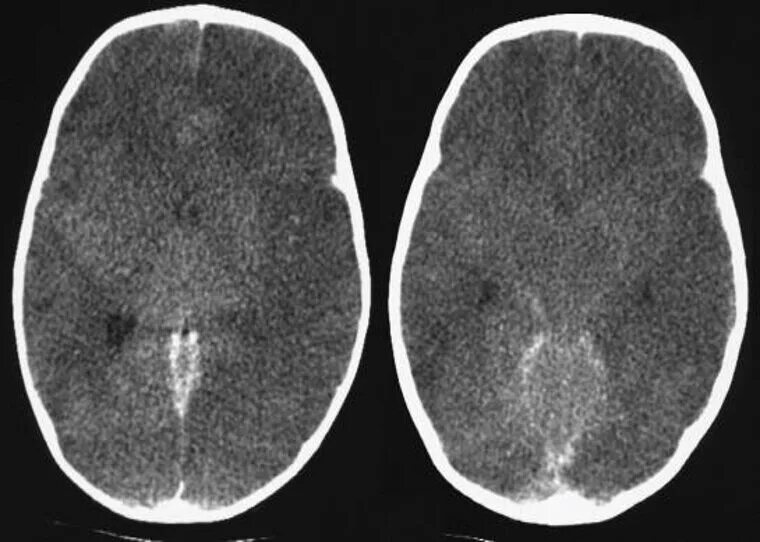

Отек головного мозга мрт